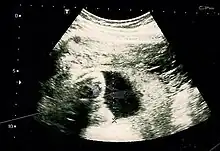

- Fetus at 17 weeks

- Fetus at 20 weeks

Obstetric ultrasonography is routinely used for dating the gestational age of a pregnancy from the size of the fetus, determine the number of fetuses and placentae, evaluate for an ectopic pregnancy and first trimester bleeding, the most accurate dating being in first trimester before the growth of the foetus has been significantly influenced by other factors.[22] Ultrasound is also used for detecting congenital anomalies (or other foetal anomalies) and determining the biophysical profiles (BPP), which are generally easier to detect in the second trimester when the foetal structures are larger and more developed.[23]

X-rays and computerized tomography (CT) are not used, especially in the first trimester, due to the ionizing radiation, which has teratogenic effects on the foetus.[24] No effects of magnetic resonance imaging (MRI) on the foetus have been demonstrated,[25] but this technique is too expensive for routine observation. Instead, obstetric ultrasonography is the imaging method of choice in the first trimester and throughout the pregnancy, because it emits no radiation, is portable, and allows for realtime imaging.[26]

The safety of frequent ultrasound scanning has not been confirmed. Despite this, increasing numbers of women are choosing to have additional scans for no medical purpose, such as gender scans, 3D and 4D scans.[27] A normal gestation would reveal a gestational sac, yolk sac, and fetal pole.[28]

The gestational age can be assessed by evaluating the mean gestational sac diameter (MGD) before week 6, and the crown-rump length after week 6. Multiple gestation is evaluated by the number of placentae and amniotic sacs present.[29]